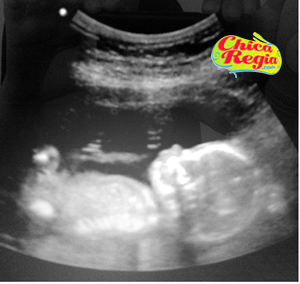

Hace una semana exactamente, nos tocó un examen muy padre llamado Ultrasonido Estructural o de Alta Definición (que se hace entre las semanas 18 y 22), en ese examen le hacen varias mediciones a mi bebé y a mi, como: medir su cabecita, cerebelo, huesitos, órganos internos, líquido amniótico, placenta, mi útero, presión sanguínea de mi bebé, etc. Todo esto con el fin de detectar o descartar problemas cromosómicos o síndromes. Al final, me dieron el video del ultrasonido y muchas fotitos.

Yo sé que comen ansias por ver a mi beba jeje (nhaa), pero con mucho carino y orgullo les muestro una hermosa foto del perfil de mi beba bella (su abdomen y cabecita), que obtuve del video del ultrasonido. ¡Ayyy! me dan ganas de agarrarla a besitos!!!